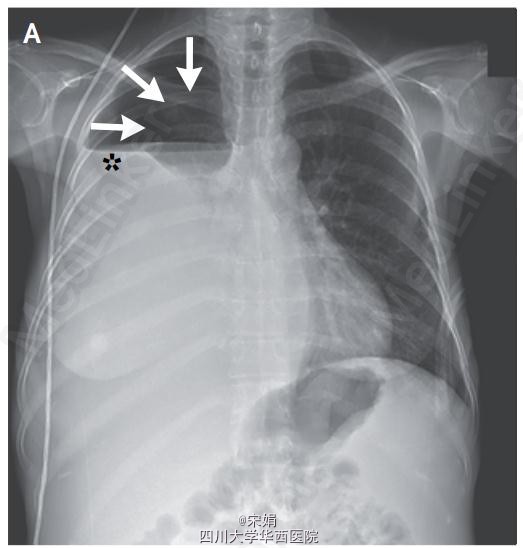

患者为46岁女性,呼吸困难就诊,患者因终末期肝病出现复发性肝性胸水,需要反复胸腔穿刺。胸部检查发现右肺无呼吸音。胸片显示液气胸(图A,箭头显示气胸,星号显示液胸)。遂留置猪尾导管引流胸腔积液,但气胸仍持续存在(图B,箭头)。